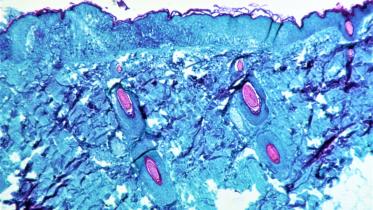

Good news: Smallpox vaccine 85% effective in preventing monkeypox

Several cases of monkeypox have been detected in North America and Europe since early May, sparking concern that the disease, endemic in parts of Africa, is spreading.